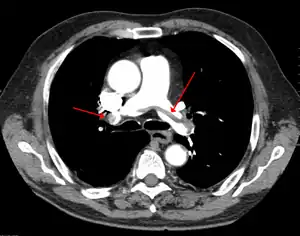

| Chest spiral CT scan with radiocontrast agent showing multiple filling defects both at the bifurcation ("saddle" pulmonary embolism) and in the pulmonary arteries | |

CT pulmonary angiography showing a "saddle embolus" at the bifurcation of the main pulmonary artery and thrombus burden in the lobar arteries on both sides.